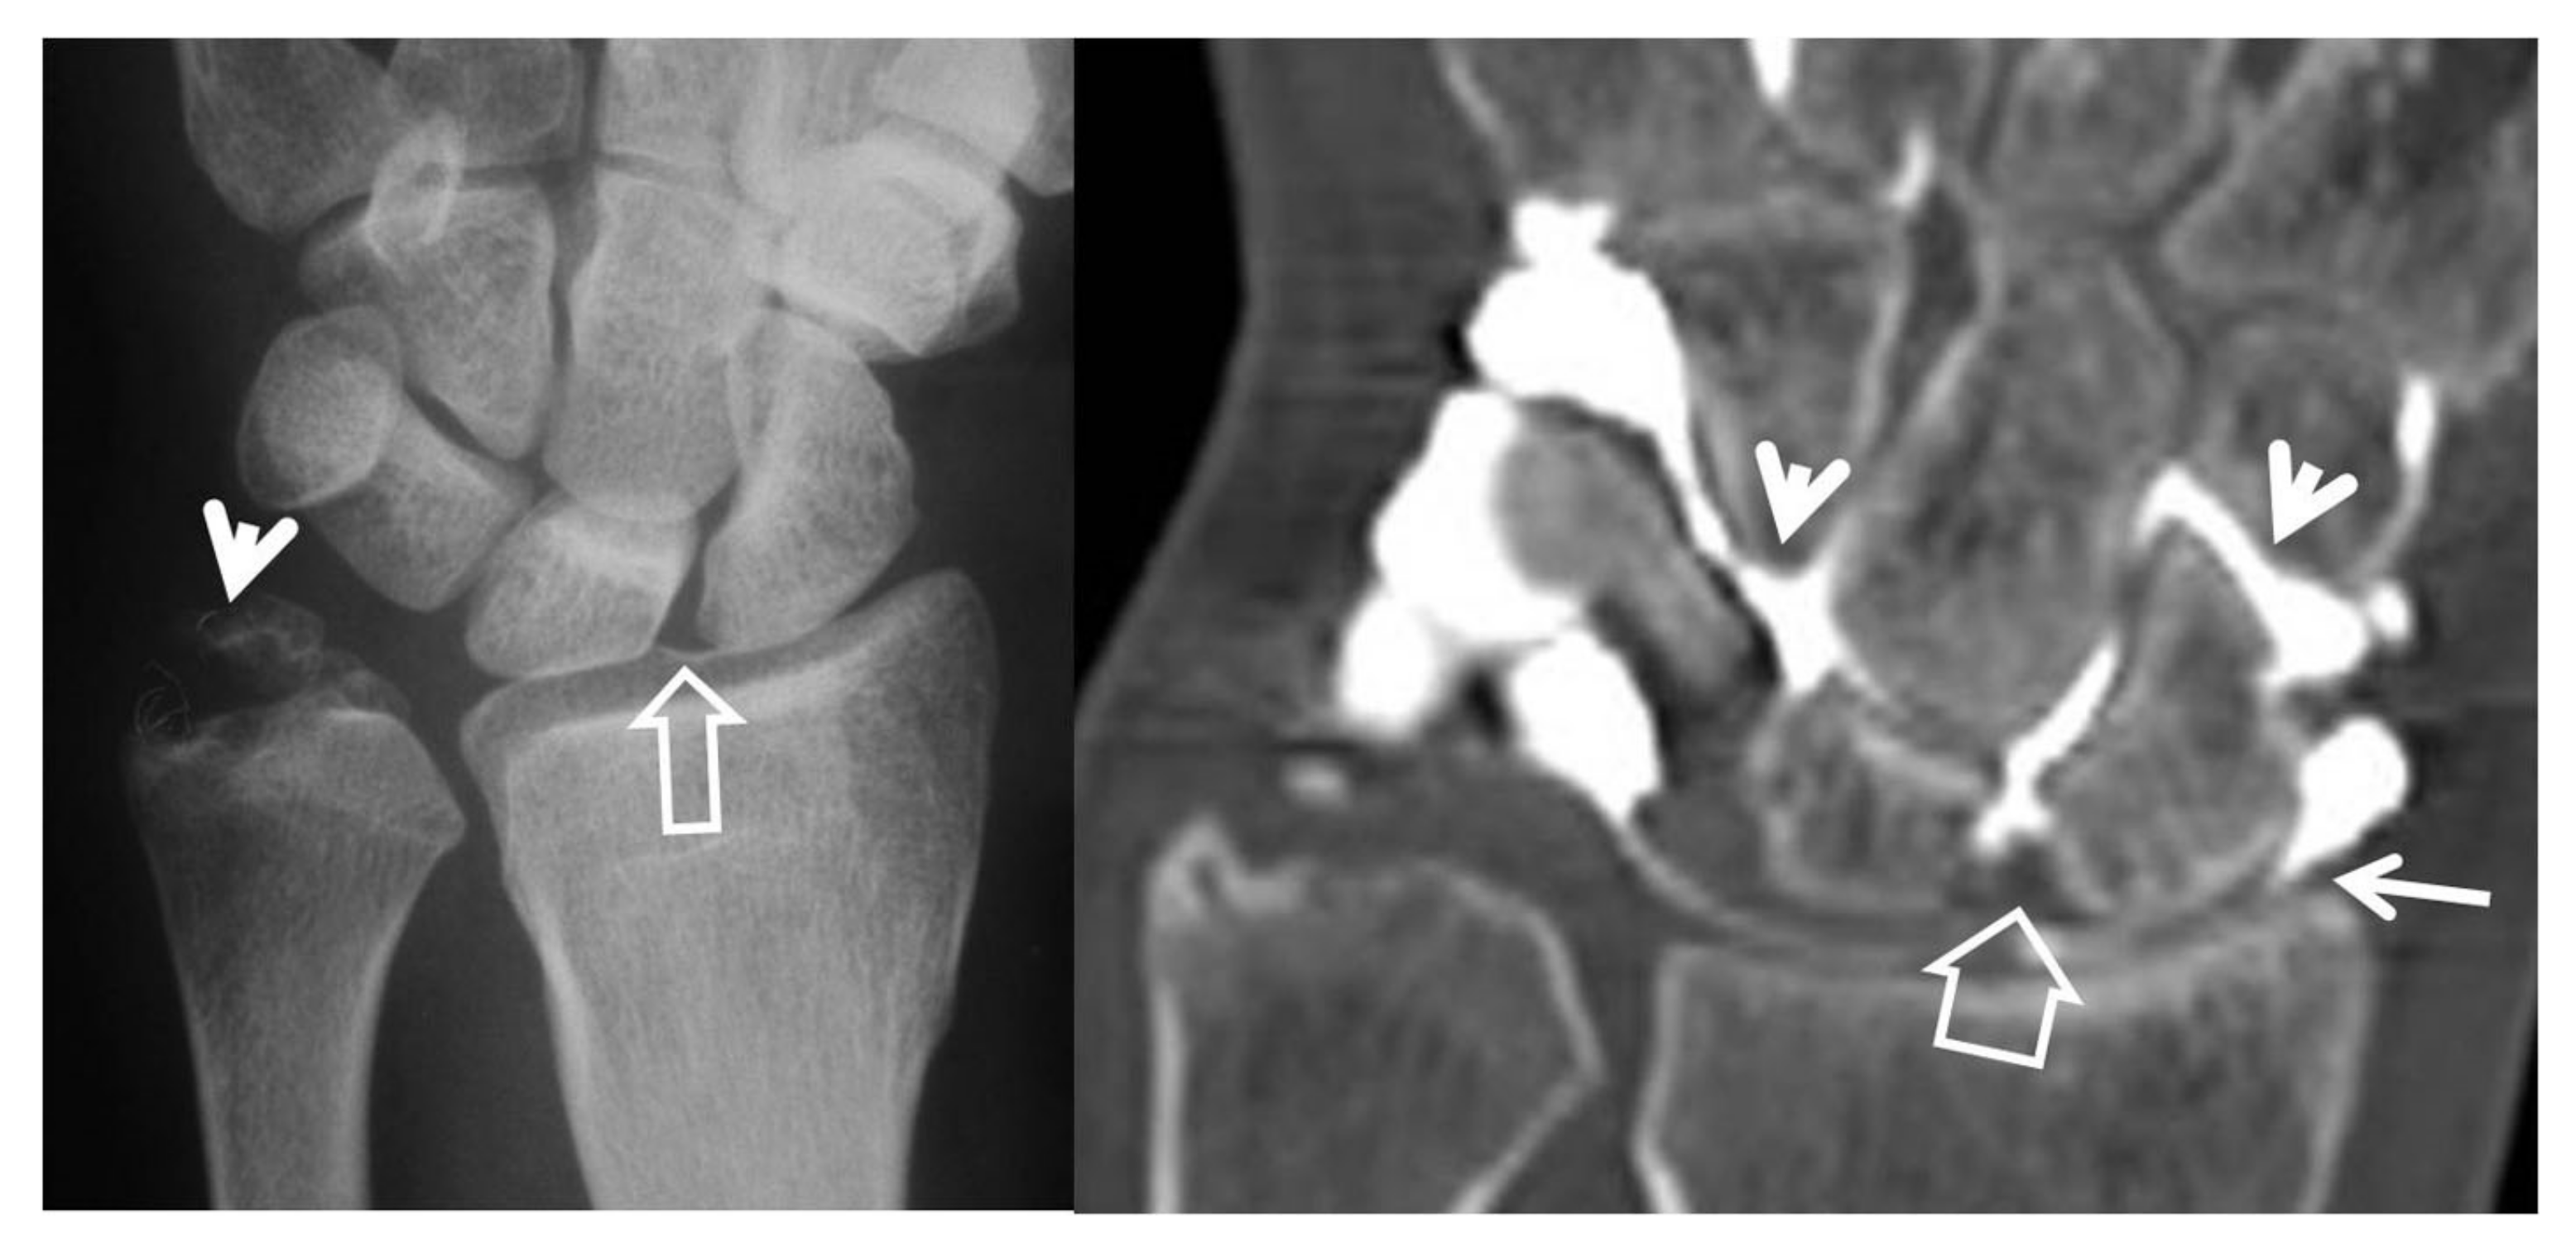

Figure 7.

A 24-year-old female athlete with a surgically proven scapholunate ligament disruption. PA radiograph (left) image shows scapholunate diastasis (open arrow) and an old fracture of the ulnar styloid (arrowhead). Coronal MDCT arthrographic image (right) shows midcarpal joint opacification (arrowheads) although the SLL looks intact (open arrow). The injection site was distal to the radial styloid (thin arrow). A small dorsal SLL tear was found in the theatre.

CT-arthrography (CTa) is performed with an iodine contrast material injected in specific wrist joints. For depicting a SLL tear, a single injection at the radioscaphoid joint is performed in our department under fluoroscopic or ultrasound guidance. In the presence of a tear, the midcarpal joints will be opacified (Figure 8).

Figure 8.

A 33-year-old with a history of scaphoid fracture. (A) Coronal CT-arthrographic image showing the scaphoid pseudarthrosis (open arrow), a radial styloid process fracture (arrowhead) and an intact scapholunate ligament (arrow). (B) Axial CT-arthrographic image showing the intact dorsal (arrow) and palmar (open arrow) parts of the scapholunate ligament. A 56-year-old male patient who was involved in a motor vehicle accident 1 year prior to current imaging. Coronal (C) and axial (D) CT-arthrographic images showing a tear at the membranous (arrow) and palmar (open arrow) parts of the scapholunate ligament.